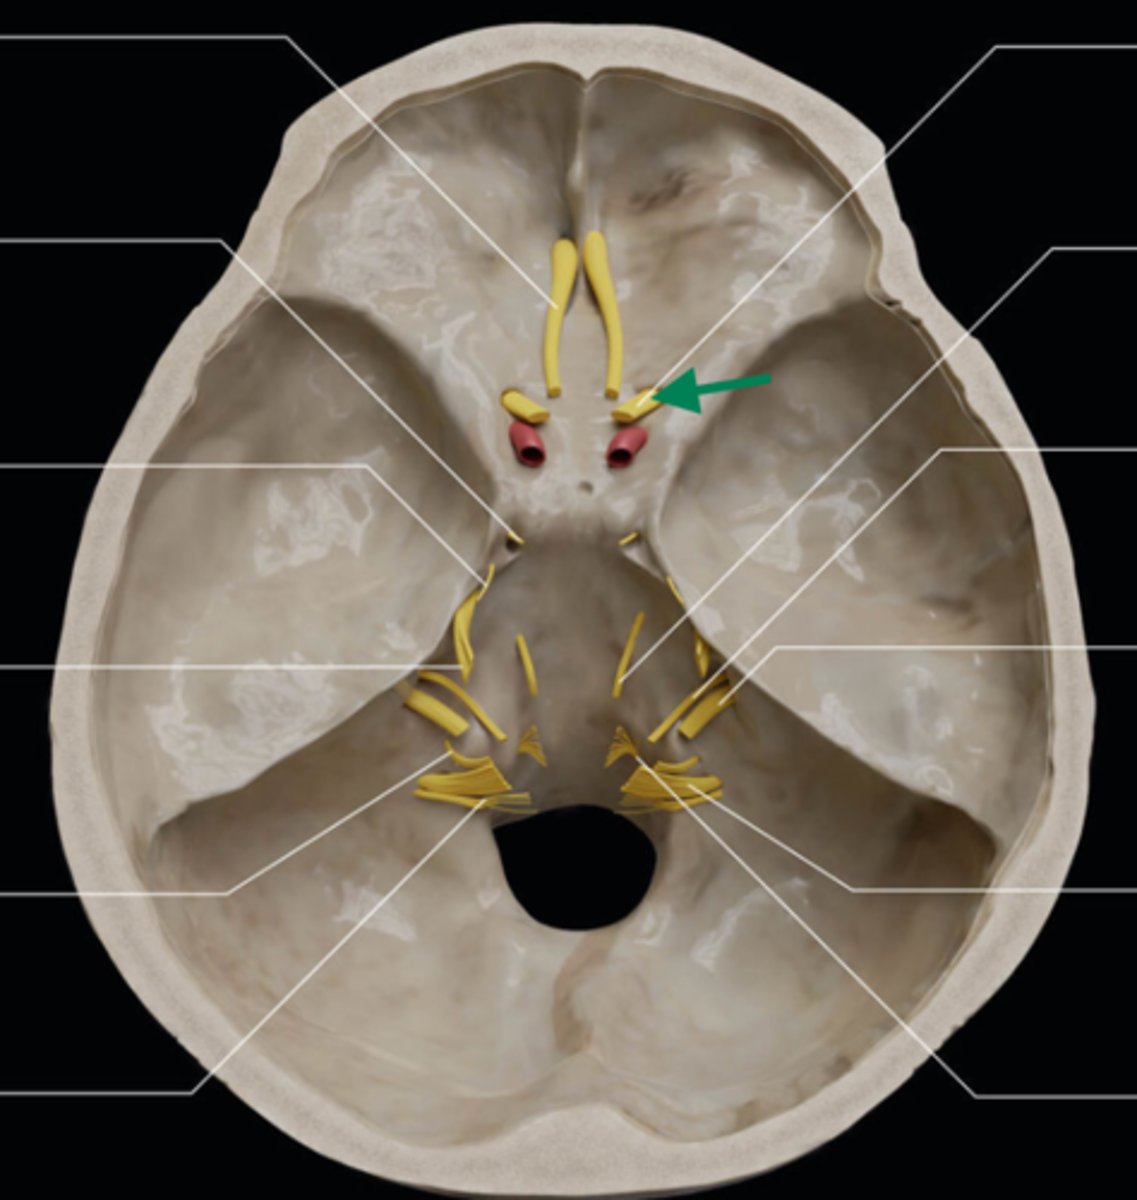

olfactory bulb

olfactory tract

optic nerve (CN II)

internal carotid artery

oculomotor nerve (CN III)

trochlear nerve (CN IV)

abducent nerve (CN VI)

trigeminal nerve (CN V)

facial nerve (CN VII)

vestibulocochlear nerve (CN VIII)

glossopharyngeal nerve (CN IX)

vagus nerve (CN X)

accessory nerve (CN XI)

hypoglossal nerve (CN XII)

optic chiasm

trigeminal ganglion

anterior cranial fossa